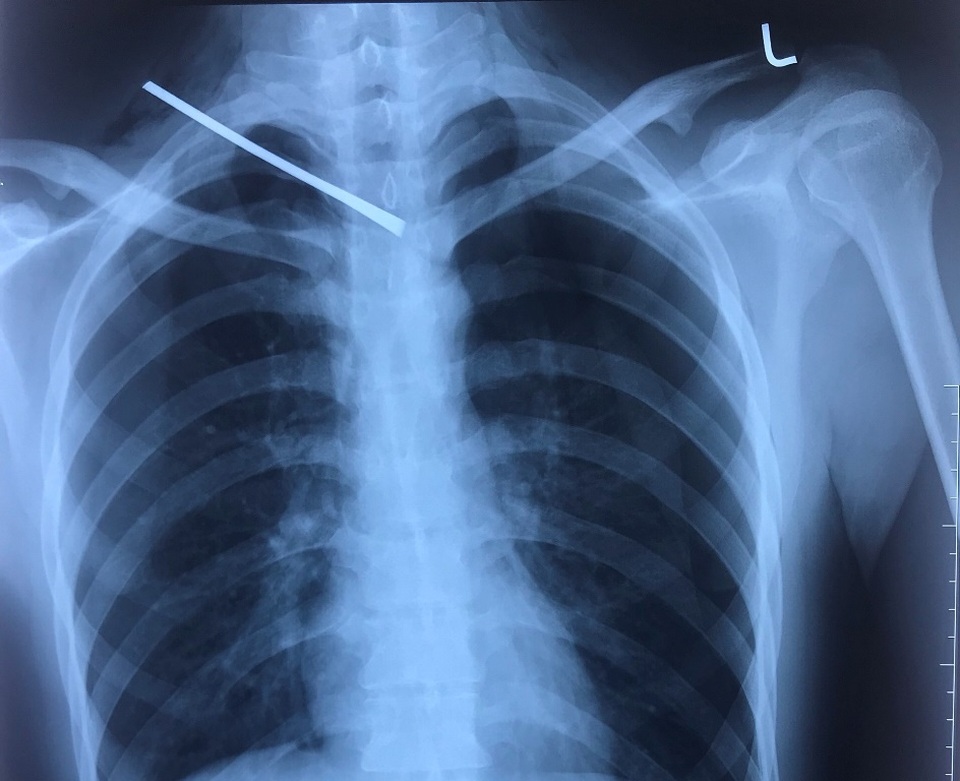

Bệnh nhân được thực hiện các xét nghiệm, kết quả X-quang tim phổi thẳng cho thấy: một dị vật cản quang từ vùng cổ phải xuyên xuống đoạn gian đốt sống D3/D4, tràn khí màng phổi hai bên.

Kết quả chụp CT Scanner cột sống cổ không cản quang cho thấy: dị vật kim loại đường kính 0.5cm dài 10cm xuyên từ vùng cổ phải đến khe gian đốt sống D3/D4 chèn vào mặt trước ống tủy, tụ khí dưới da vùng cổ ngực hai bên, tràn khí và ít dịch màng phổi phải, tràn khí màng phổi trái.